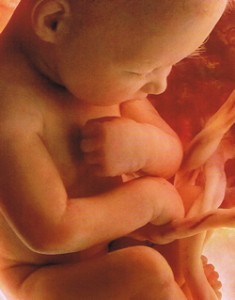

38 nedelya beremennosti 64 foto chto proishodit s malyshom i mamoj predvestniki rodov u povtornorodyashih i pervorodyashih seks i priznaki priblizhayushihsya rodov vtoraya beremennost toshnota i ponos izzhoga na 38 akusherskoj nedele (Тип файла jpg)

38 Nedelya Beremennosti 64 Foto Chto Proishodit S Malyshom I Mamoj Predvestniki Rodov U Povtornorodyashih I Pervorodyashih Seks I Priznaki Priblizhayushihsya Rodov Vtoraya Beremennost Toshnota I Ponos Izzhoga Na 38 Akusherskoj Nedele